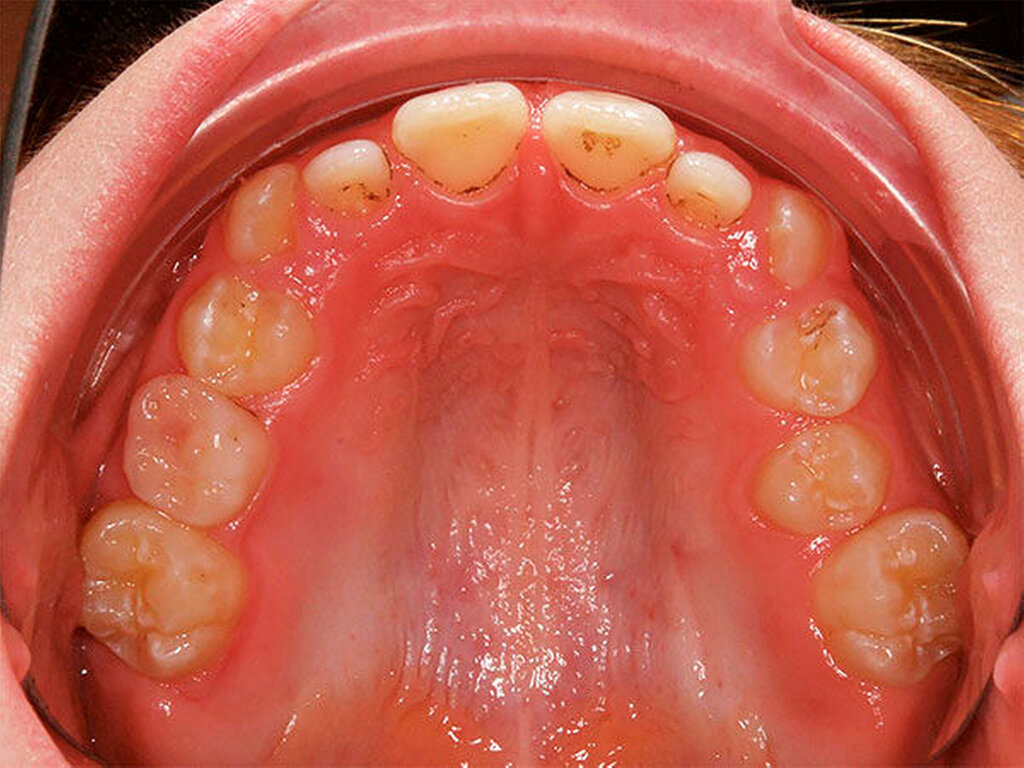

Ausgeprägte Zahnfehlstellungen und Gebissanomalien zeigen sich im reinen Milchgebiss deutlich seltener als im Wechsel- oder im permanenten Gebiss [Schopf, 2003]. Dennoch sollten bereits in dieser frühen Phase beispielsweise die Platzverhältnisse für die später durchbrechenden Zähne beurteilt werden. Im Säuglingskiefer liegen die Zahnkeime der Milch-Inzisiven zunächst in einer sagittalen Staffelstellung [van der Linden, 1980]. Die mit dem Durchbruch der Milchzähne einhergehende Bildung des Alveolarfortsatzes und die wachstumsbedingte Vergrößerung der Zahnbögen führt meist zu einer lückigen Stellung der Milchschneidezähne [Sillman, 1964] (Abbildung 1). Diese Lücken tragen dazu bei, den deutlich breiteren bleibenden Nachfolgern eine regelrechte Einordnung in den Zahnbogen zu ermöglichen [Moyers, 1976; Leighton, 1978]. Ein „schönes“, lückenloses Milchgebiss oder gar Engstände in der Front sind ein Alarmsignal im Hinblick auf spätere Platzprobleme für die bleibenden Zähne [Leighton, 1969]. Bei diesen Patienten ist eine intensive Überwachung während des Zahnwechsels der permanenten Inzisiven ratsam, um gegebenenfalls rechtzeitig Platz schaffende Maßnahmen einleiten zu können.